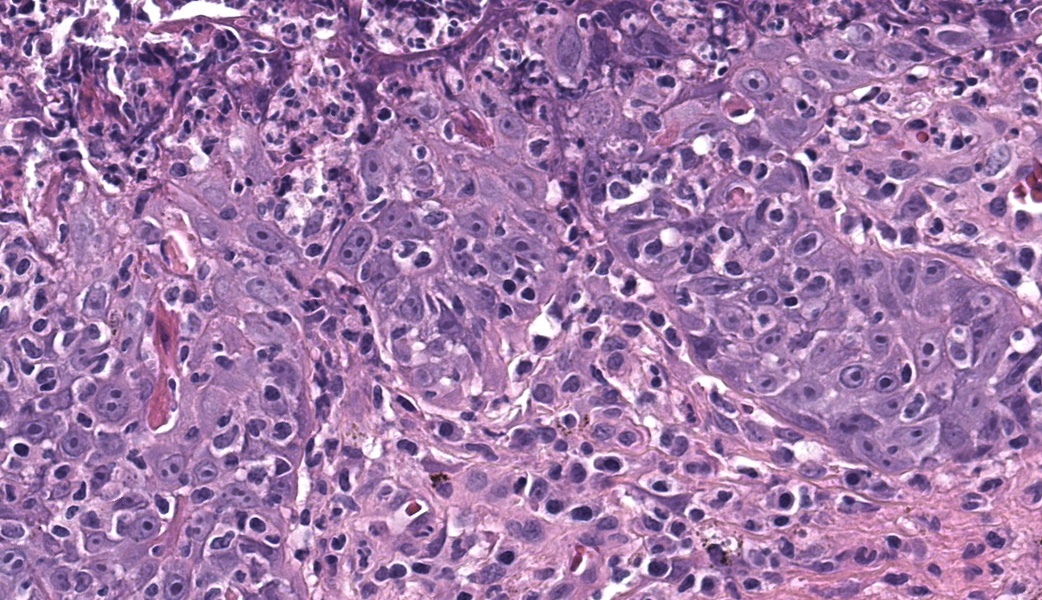

Haired skin. Alle the biopsies are histologically similar. The superficial and mid dermis is obscured by a moderate to severe inflammatory infiltrate, often obscuring the dermo-epidermal junction. The inflammatory infiltrate is represented by a prevalence of lymphocytes and plasma cells, macrophages occasionally engulfing melanin (melanophages), and rare neutrophils. The epidermis is moderately thickened (irregular hyperplasia), with mild intercellular edema (spongiosis) and severe thickening of the stratum corneum by predominantly nucleated (parakeratotic hyperkeratosis) or less frequently non-nucleated keratin (orthokeratotic hyperkeratosis). Numerous apoptotic figures are observed throughout the epidermis, occasionally surrounded by lymphocytic satellitosis. Similar lesions are observed in the hair follicles. There is multifocal erosion or ulceration of the epidermis; the ulcerated areas are obscured by serocellular crusts.Contributor's Morphologic Diagnoses:

Histologically, EM has the features of a cytotoxic (interface) dermatitis. Necrotic keratinocytes are present throughout the epidermis and the adnexal epithelia, often associated with lymphocytic satellitosis. The dermopidermal junction is obscured by lymphocytes and macrophages. Basal keratinocytes could be degenerated.3,5,6 Hyperkeratosis and parakeratosis are commonly seen in canine EM, as opposed to human EM, and may be severe in persistent forms of EM.6 This latter form is called “hyperkeratotic EM”.1

This classic case of erythema multiforme (EM) was much appreciated by participants as it stimulated great discussion on EM and other top differentials, cytotoxic dermatitis pathogenesis, and a handful of “boards-worthy” information. The contributor’s well-written and thorough comment covers much of what was discussed in conference related to the differences between the human and canine manifestations of EM, so focus will be placed on other major discussion points.The major histologic features to help differentiate EM from other conditions are the presence of suprabasilar and transepidermal apoptosis of keratinocytes and satellitosis of lymphocytes around affected keratinocytes.5 Note, however, that if lymphocytes are instead aggregating in and near the epidermis rather than just hovering around affected keratinocytes, epitheliotropic T-cell lymphoma should rise on the differential list. In EM, epithelial dysplasia may also be seen secondary to the concurrent inflammation and necrosis. The same features of transepidermal apoptosis and lymphocyte satellitosis can also be seen in the follicular epithelium, not just in the epidermis! Follicular epithelium may also exhibit hyperpigmentation and vacuolation secondary to inflammation. Parakeratotic hyperkeratosis is often seen in the hyperkeratotic form of EM but is not considered a key diagnostic feature of EM in general.1,5

In keeping with current dermatopathology terminology, EM is classified as a cytotoxic dermatitis. Other entities that fall under this designation include SJS/TEN, graft-vs-host disease, and cutaneous viral infections (i.e. poxvirus). Both EM and SJS/TEN are mediated by cytotoxic CD3+/CD8+ lymphocyte responses against keratinocytes that have been altered either due to infectious agents or drugs.6 Apoptosis results from either direct cytotoxicity or through soluble mediators such as Fas ligand, granzymes, perforin, and granulysin.1,6 For those taking the Phase I exam soon, Fas ligand should ring a bell as the ligand that binds to the Fas death receptor in extrinsic apoptosis.